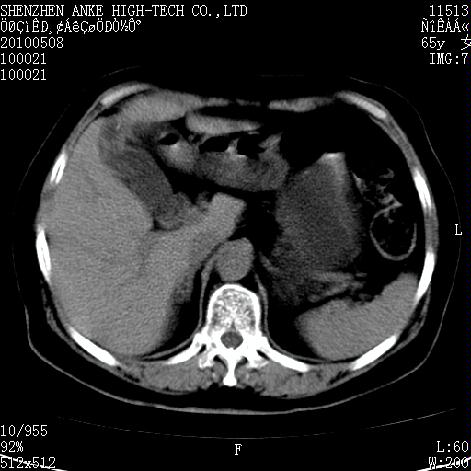

女,65岁。乳腺ca术后多年。现在剧烈腹痛待查。b超示胆囊炎、胆结石。

左侧乳腺癌术后,胸骨柄见有骨质破坏,考虑乳腺癌骨转移,胆囊炎,右肾囊肿。

1)胆囊炎。2)右肾囊肿。3)左侧少量胸腔积液。4)建议行ect检查排除胸骨转移瘤。

1)胆囊结石、胆囊炎。2)右肾囊肿占位。3)左侧少量胸腔积液。4)建议行ect检查排除胸骨转移瘤。

5)调整窗宽、窗位注意观察腹腔内有否游离气体(能看清腹内脂肪及气体)。